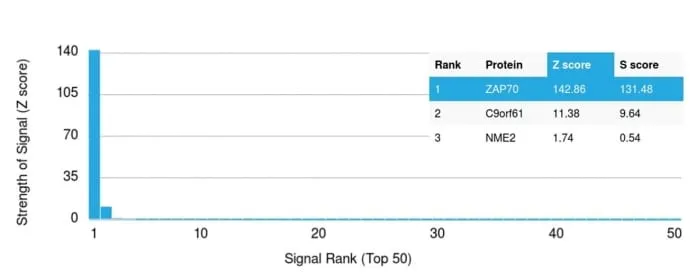

ZAP70 is a 70 kDa protein tyrosine kinase found in T-cells and natural killer cells. Control of this protein translation is via the IgVH gene.ZAP70 protein is expressed in leukemic cells of approximately 25% of chronic lymphocytic leukemia (CLL) cases as well. Anti-ZAP70 expression is an excellent surrogate marker for the distinction between the Ig-mutated (anti-ZAP70 negative) and Ig-unmutated (anti-ZAP70 positive) CLL subtypes and can identify patient groups with divergent clinical courses. The anti-ZAP70 positive Ig-unmutated CLL cases have been shown to have a poorer prognosis._x000D_ _x000D_ Primary antibodies are available purified, or with a selection of fluorescent CF® Dyes and other labels. CF® Dyes offer exceptional brightness and photostability. Note: Conjugates of blue fluorescent dyes like CF®405S and CF®405M are not recommended for detecting low abundance targets, because blue dyes have lower fluorescence and can give higher non-specific background than other dye colors._x000D_Synonyms: